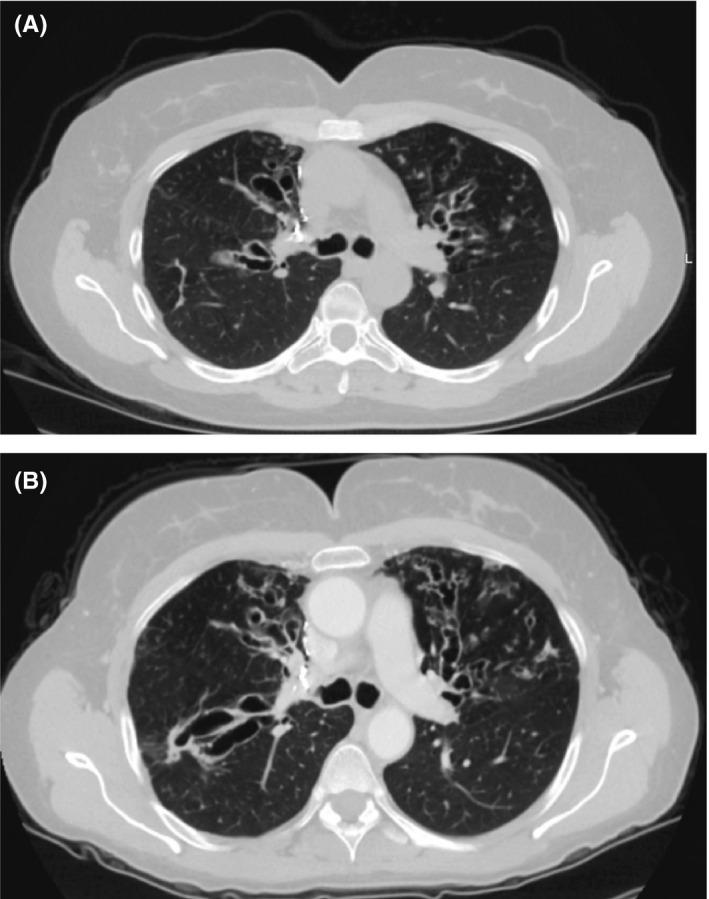

Fighting diagnostic confirmation bias: Cystic fibrosis, allergic bronchopulmonary aspergillus, or both?

As diagnostic algorithms for cystic fibrosis (CF) continue to evolve, education of general practitioners is essential to prevent delayed diagnosis of CF and allow prompt referral to CF centers. For patients suffering from allergic bronchopulmonary aspergillosis (ABPA), CF should be at the top of the differential diagnosis.